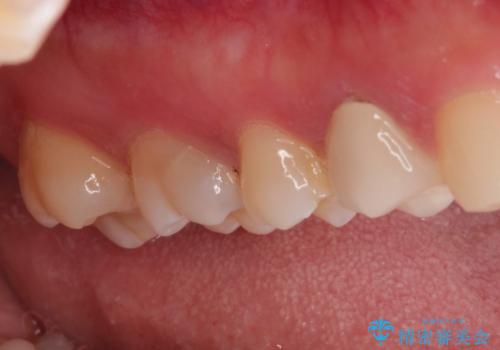

【VPT(歯髄温存療法)とセラミックインレー】深い虫歯でも神経を残したい

- 虫歯が大きく神経まで達していたので、VPT(歯髄温存療法)を行って細菌感染した部分の神経のみ取り除き、保存可能な神経は保存し被せ物はセラミックインレーで治療を行いました。

- 121,000円(VPT:44,000円 セラミックインレー:77,000円)費用は治療当時の料金となります